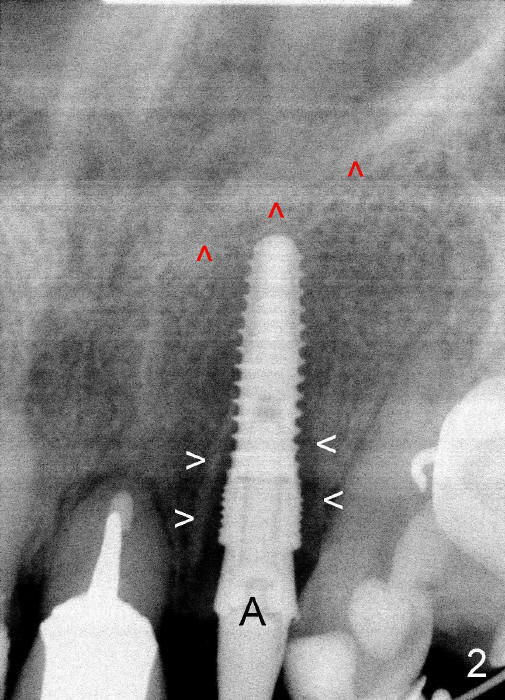

A prominent feature of implant failure in this case is pain. The patient feels that the pain is from the base of the nose. PA taken 3 days postop shows that the implant is inferior to the nasal floor (Fig.2 red ^). Clinically, the buccal gingiva continues to be erythematous 10 days postop (Fig.1). The pain is so unbearable that the implant (3.8x14 mm) is removed 10 days post placement. After repeated debridement, a 4.1 mm tap (Fig.3 T) is manually inserted with torque. A 4.1x14 mm submerged implant is placed with insertion torque < 30 Ncm, but it is placed subcrestally (Fig.4 <--). This time an immediate provisional is not provided. The flap is sutured. The pain disappears immediately. No infection is found 7 days postop (Fig.5). However, an asymptomatic vesicle is noted at the crest 3 weeks postop (Fig.6). The gingiva looks normal 2 and 3 months postop (Fig.7,8). The coronal gap dissolves 3 months postop (Fig.9 >, as compared to Fig.4), suggesting osteointegration. The implant is uncovered 4 months postop (Fig.10). Bracket is placed 5 months postop (Fig.10'). One month later, the left central incisor improves in position coronocervically (Fig.11), but the overjet needs correction by distalization of the upper anterior teeth. The implant at the site of #10 may be used as an anchorage.